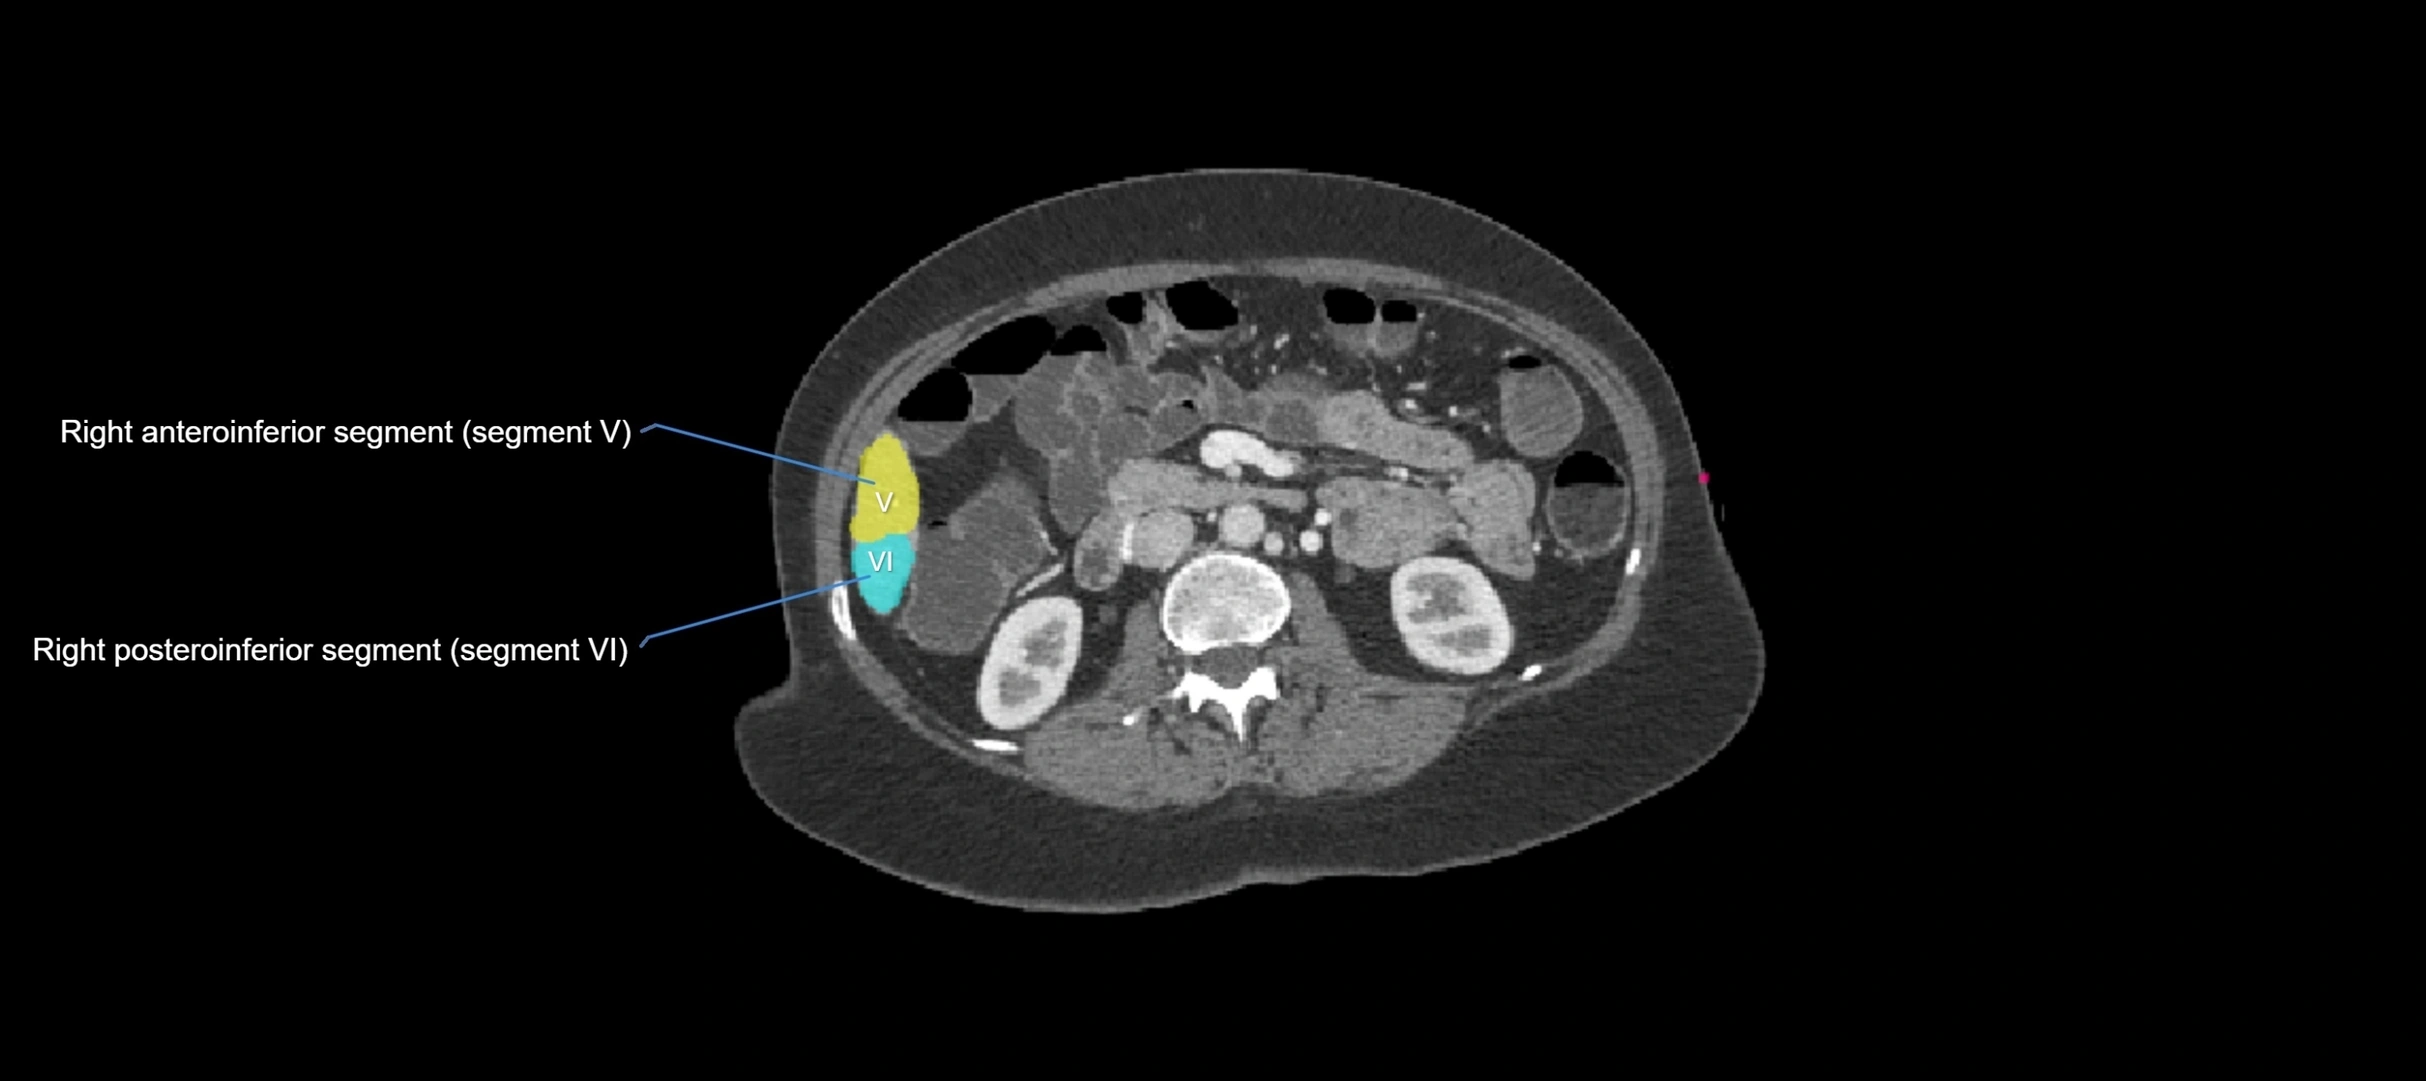

CT Image

image